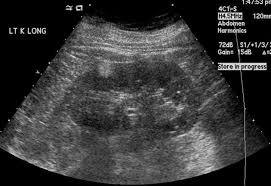

Ultrasound Kidney Upper Pole. Transverse a and longitudinal b views of the left kidney show a dilated obstructed upper pole collecting system and proximal ureter u. What is a questionable punctate calcific density in the kidney ct report says that.

Pyelonephritis Of The Upper Pole Longitudinal Urinary Tract Reproductive System Sonography

Each kidney is screened in sagital and transverse plane fig.